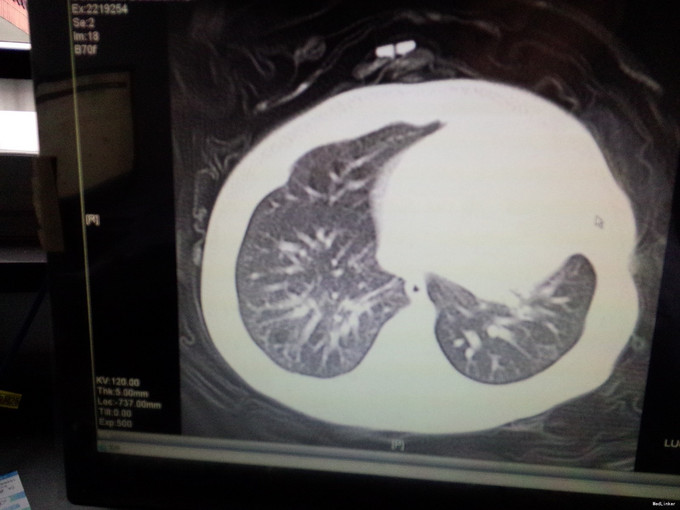

女,4月,咳嗽4-5天,加重一天。4-5天出现咳嗽,不发热,在诊所就诊予以对症处理(具体用药不详),疗效不佳,咳嗽症状加重,气促明显,近2天患儿吃奶差,无呕吐,大便呈稀水样改变。体检:神清,精神差,呼吸急促50次i/分,HR140次/分,两肺可闻及明显的湿罗音,心脏未闻及明显病理性杂音。肺部CT提示肺不张,心脏B超提示室间隔缺损(基底部)。血RT:WBC16.87*109/l,免疫球蛋白水平低.

呼吸急促50次i/分,HR140次/分,两肺可闻及明显的湿罗音,心脏未闻及明显病理性杂音。肺部CT提示肺不张,心脏B超提示室间隔缺损(基底部)。血RT:WBC16.87*109/l,免疫球蛋白水平低.